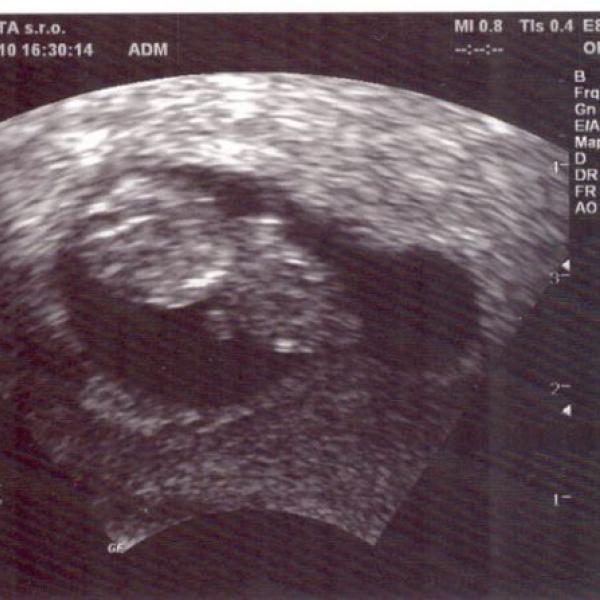

zítra mě čeká další UZ v 9. týdnu, mám za sebou UZ s potvrzením těhotenství (těh. váčku), pak v 6. tydnu potvrzení srdeční činnosti. Tak se těším na zítřek, že zase uvidím ten svůj poklad a doufám, že bude vše ok. Na mimi jsme čekali delší dobu, ale nakonec nám v centru pro IVF hodně pomohli a otěhotněla jsem i bez umělého oplodnění ;) Hrozně se těším, jak v květnu už budu mít u sebe toho broučínka ...Všem vám přeji jen to dobré a hodně radosti se svých očekávaných pokladů. krásný den a opatrujte se Jana